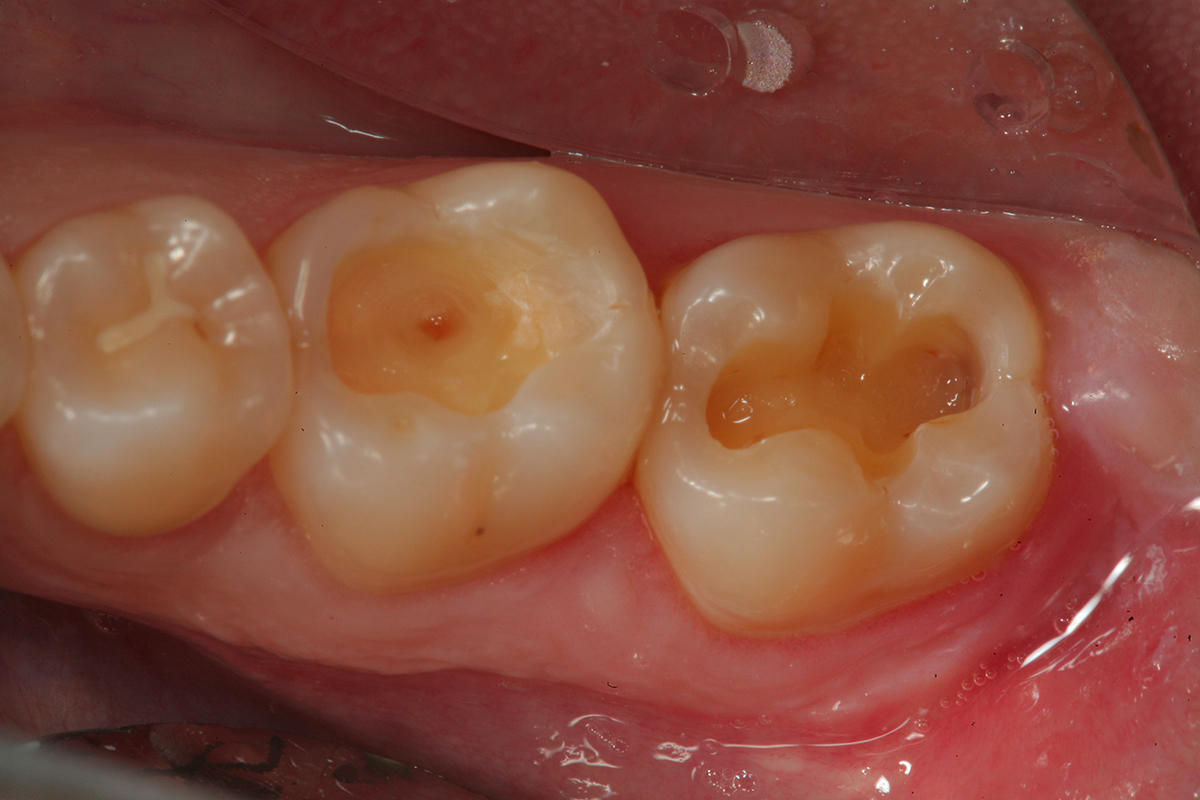

Fig 11. The preparation on tooth No. 19 is disinfected with 2% chlorhexidine solution (ConsepsisTM, Ultradent Products) after the bleeding site was controlled with a diode laser. A bioactive cavity liner (TheraCalTM LC, Bisco Dental Products) was then placed over the exposure and light cured. Next, a bioactive “dentin replacement” material (TheraBase®, Bisco Dental Products)  was used to base both cavity preparations to a more ideal depth just apical to the dentinoenamel junction.

Figure 11